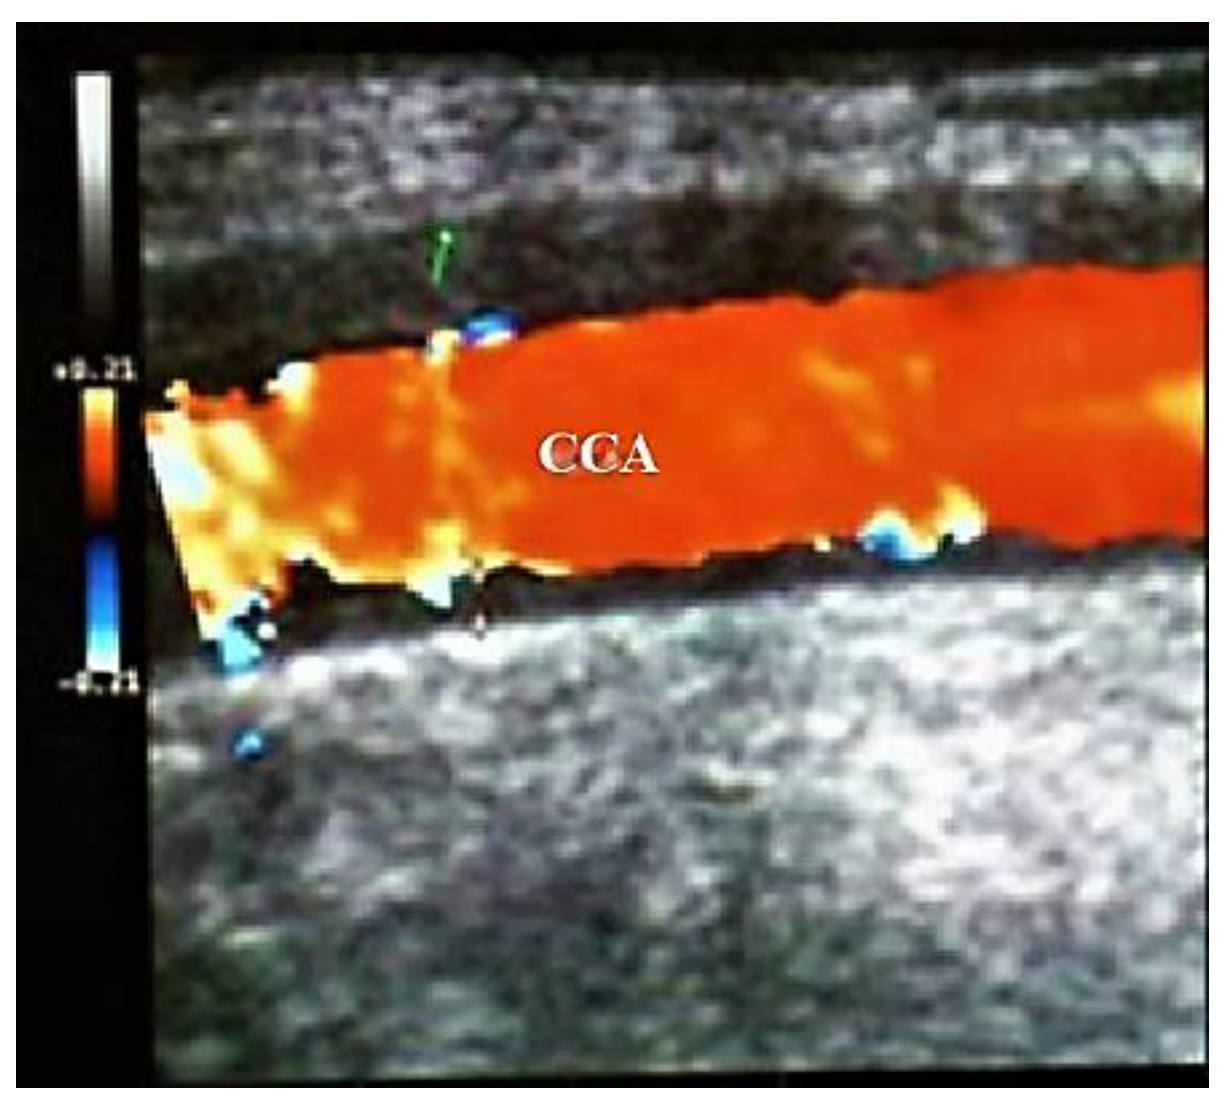

- Large size arteries: the common carotid arteries (CCAs), the ECAs, the internal carotid arteries (ICA’s), the vertebral, the subclavian, and the axillary arteries,

3.3. Duplex and Color-Coded Duplex Sonography of the Large Cervical and Cervico-Brachial Vessels

- US image of wall thickening (“halo”) is brighter in Takayasu arteritis than in GCA, because the patient with GCA has a larger mural edema than in Takayasu arteritis (GCA being a more acute disease than Takayasu arteritis) [30].